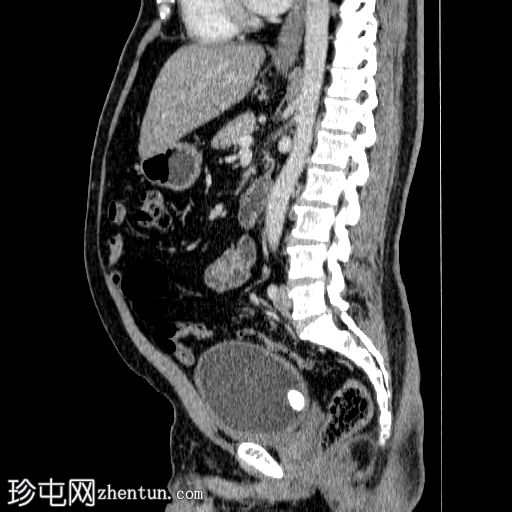

轴位增强扫描

动脉期

在左侧输尿管膀胱连接处可见一枚24×15 mm的大膀胱结石。膀胱壁轻度弥漫性增厚,厚度约6 mm,提示膀胱炎。

左肾上极发现一单纯性皮质囊肿,Bosniak I 型,大小为 13 mm。

可见多个副脾(脾小体),位于主脾实质的上方和下方,在影像学各期均表现出与脾脏相似的衰减值。

肝脏弥漫性脂肪浸润。